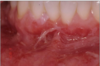

Erosive form of lichen planus

Bilateral symptomatic erythematous areas with fine white radiating striae

Central ulceration

Desquamative gingivitis → ONLY ON EROSIVE LICHEN PLANUS NOT THE RETICULAR ONE

Erosive form of lichen planus

Bilateral symptomatic erythematous areas with fine white radiating striae

Central ulceration

Desquamative gingivitis → ONLY ON EROSIVE LICHEN PLANUS NOT THE RETICULAR ONE

Erosive form of lichen planus

Bilateral symptomatic erythematous areas with fine white radiating striae

Central ulceration

Desquamative gingivitis → ONLY ON EROSIVE LICHEN PLANUS NOT THE RETICULAR ONE

Erosive form of lichen planus

Bilateral symptomatic erythematous areas with fine white radiating striae

Central ulceration

Desquamative gingivitis → ONLY ON EROSIVE LICHEN PLANUS NOT THE RETICULAR ONE

Erosive form of lichen planus

Bilateral symptomatic erythematous areas with fine white radiating striae

Central ulceration

Desquamative gingivitis → ONLY ON EROSIVE LICHEN PLANUS NOT THE RETICULAR ONE